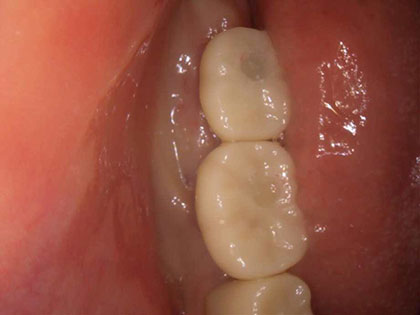

• 初診時の写真がこちら

• インプラント術前1

• インプラント術前2